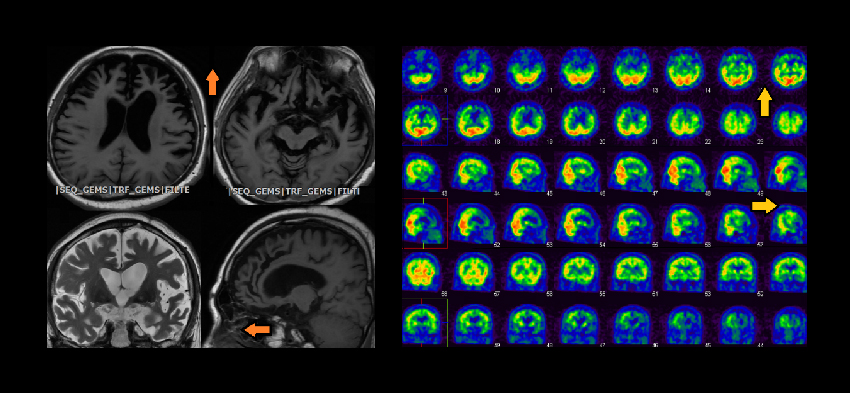

依照臨床表現與影像推斷(見下圖),額顳葉退化症(FRONTOTEMPORAL LOBAR DEGENERATION)的可能性很高。很可惜,目前沒有藥物可以治療額顳葉退化症,若使用一般用來改善阿茲海默症症狀的抗乙醯膽鹼藥物,不僅沒有效果,更可能帶來反效果。

▲ 箭頭所指為前頭(FRONTAL)方向,左圖為老柳的腦部磁振造影,顯示前方額葉與顳葉萎縮;右圖為腦血流影像,同樣顯示前額葉與顳葉血流下降,這和磁振造影顯示的腦萎縮是相互輝映的。